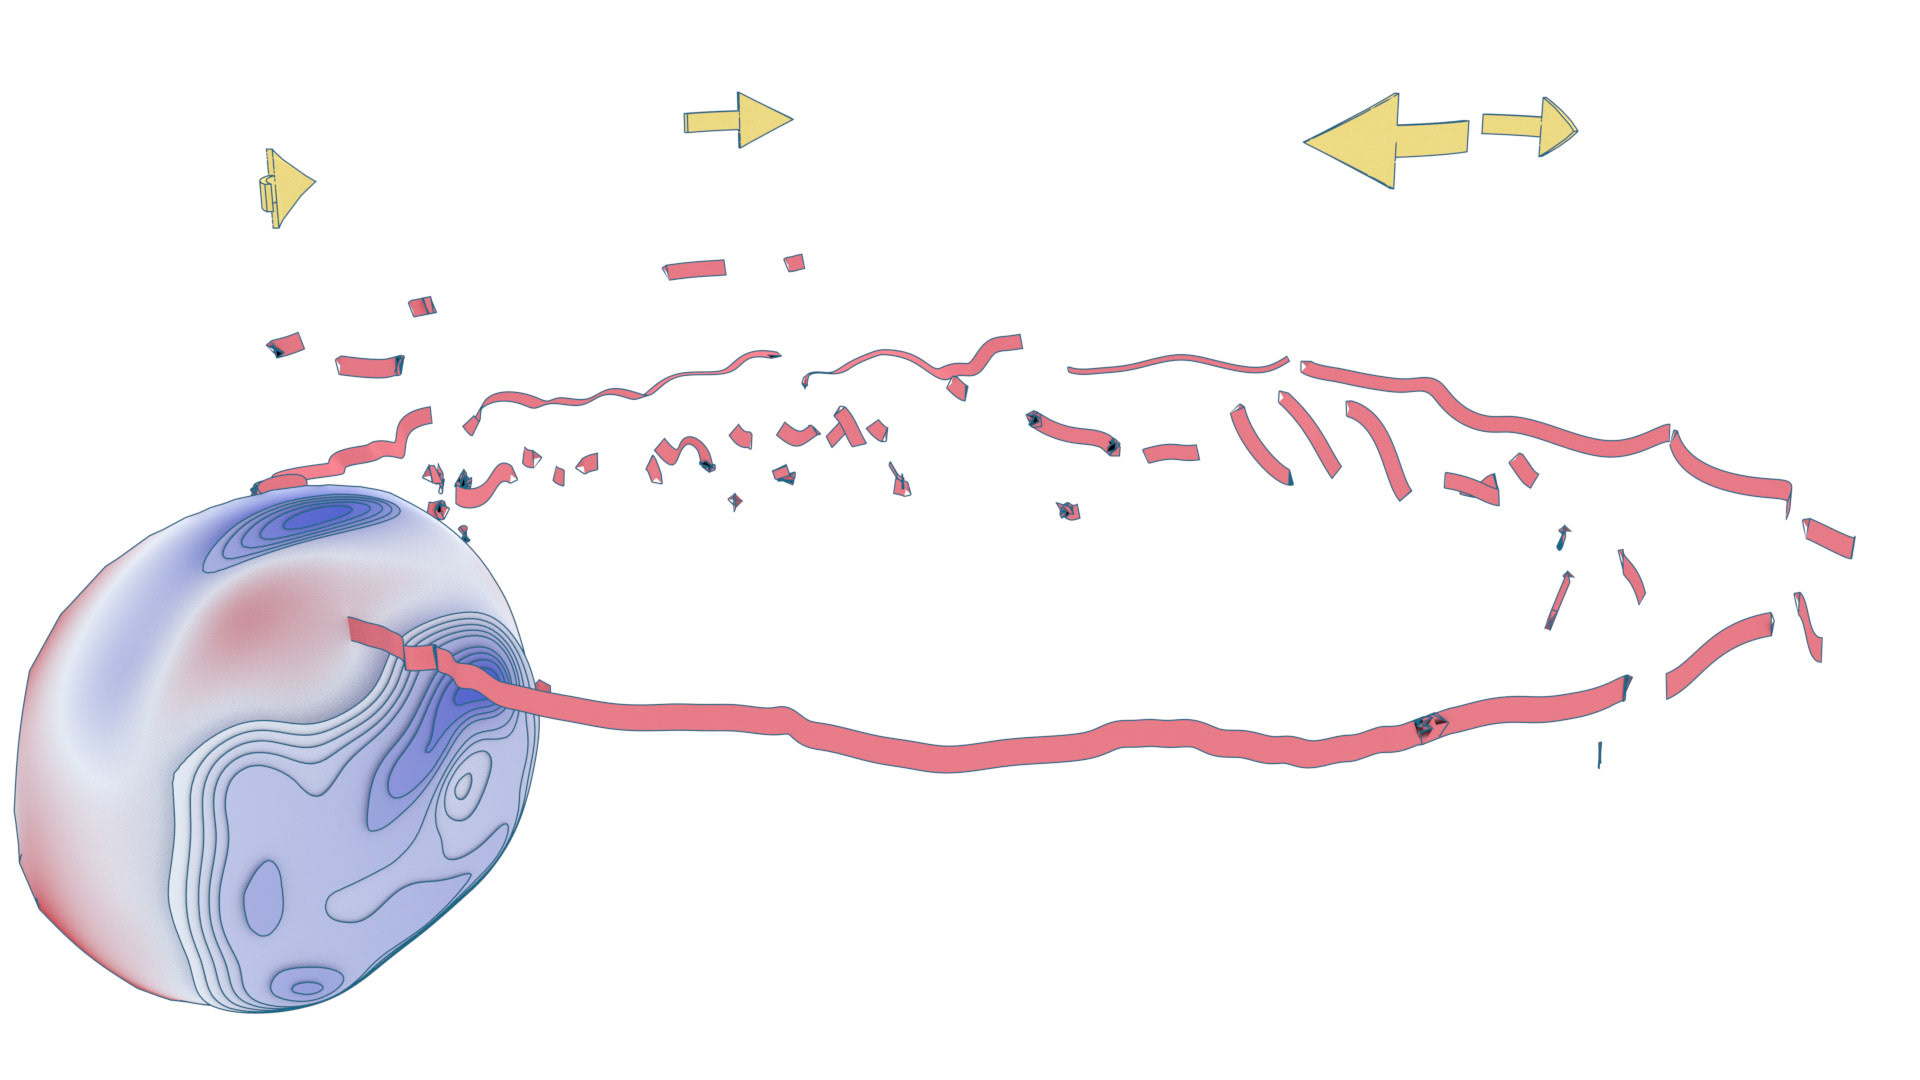

An ongoing collaboration with the Biomedical Simulation Lab (BSL), University of Toronto. In my role, I develop concept sketches and renderings that are then implemented algorithmically. The overall approach is to show turbulent flow visualizations without animation my mapping the transitions among states to carousel that corresponds to the cardiac cycle.